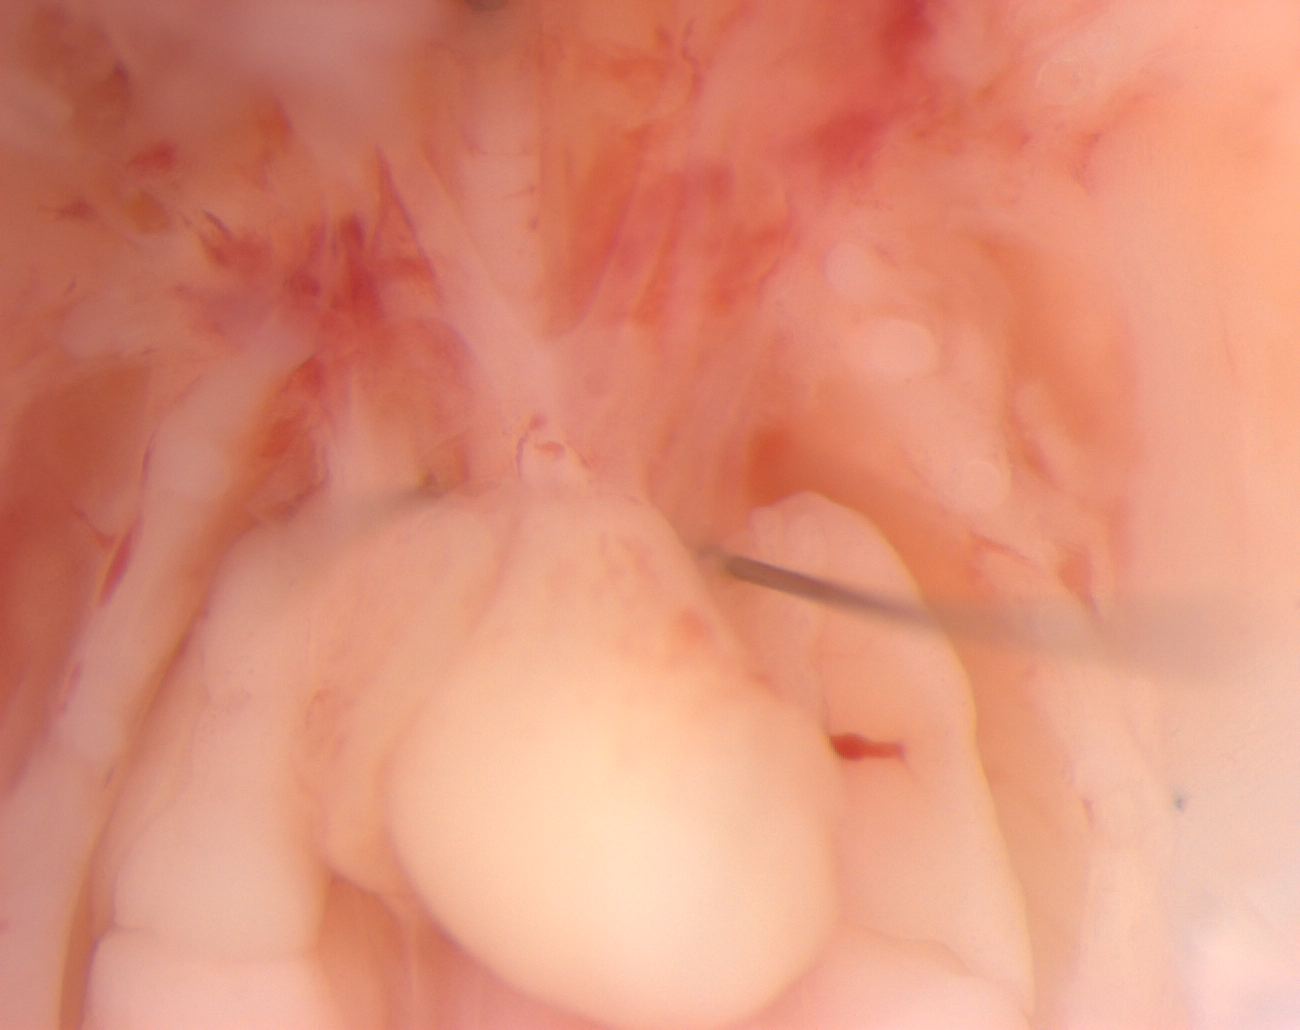

Caption Mutant 1702-003-2 (E16.5) displays malaligned great arteries indicative of double outlet right ventricle (DORV) as confirmed by ECM imaging.